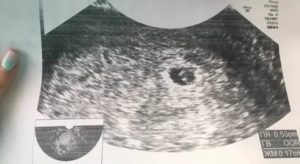

Ультразвуковое исследование в пять недель

Дать стопроцентное заключение о наступлении беременности на гинекологическом осмотре нельзя. Проведение УЗИ на 5 неделе беременности позволяет определить число оплодотворенных яйцеклеток, место прикрепления эмбриона в маточной полости, параметры матки.

На мониторе ультразвукового аппарата виден зародыш, который похож на маленького головастика, его размеры не больше косточки апельсина. У эмбриона закладываются зачатки спинного и головного мозга, которые берут свое развитие из уже сформированной нервной трубки.

На этом сроке на УЗИ можно четко рассмотреть сердцебиение еще формирующегося органа, и уже слышны сердечные ритмы зародыша. Сердечные сокращения эмбриона составляют около 100 – 120 уд. в мин. На пятой неделе сердце представлено двумя каналами, называемые сердечными трубками, которые постоянно сокращаются.